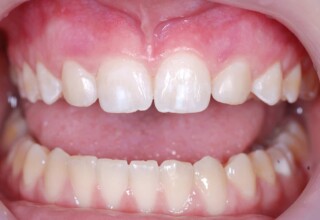

Bleaching and height increase of lower central incisor

Bleaching of vital left premolar, bleaching of all teeth and new restorations

Initial appearance

Final appearance